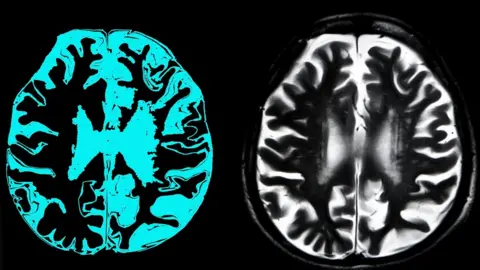

A new type of dementia

Meanwhile, experts think they have found a new form of dementia and millions may have been wrongly diagnosed.

Dementia is a symptom found in many diseases of the brain and memory loss is the most common feature.

Alzheimer's disease is the most common form of dementia and others include vascular dementia, dementia with Lewy bodies, fronto-temporal dementia, Parkinson's disease dementia, amyotrophic lateral sclerosis.

Now "limbic-predominant age-related TDP-43 encephalopathy" or more simply "Late" has been added to the list.